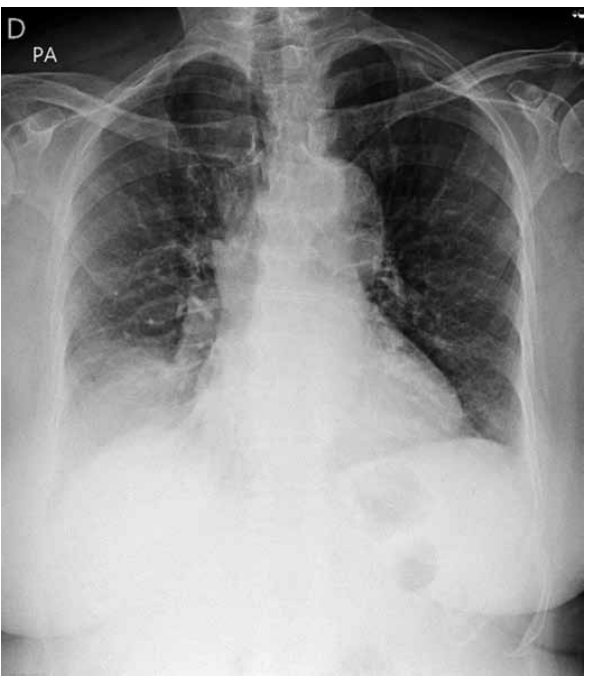

Analise a radiografia de tórax a seguir.

(Arquivo pessoal; imagem usada com autorização)

A radiografia apresenta a seguinte alteração compatível com o envelhecimento: